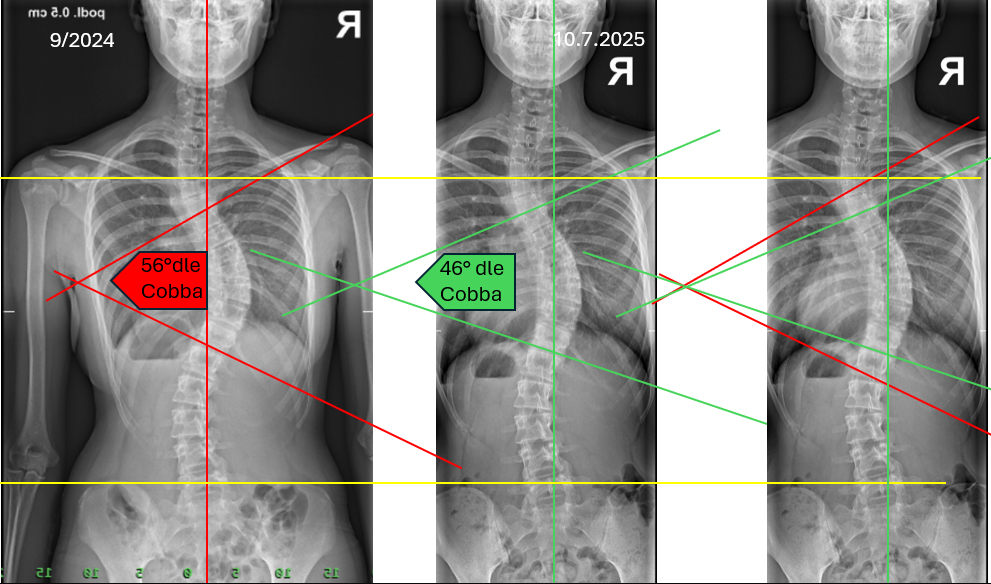

Obrázek se zlepšením u 15 leté dívky 10°Cobba za 10 měsíců – denně masírují a cvičí, chodí k nám pravidelně na kontrolu.